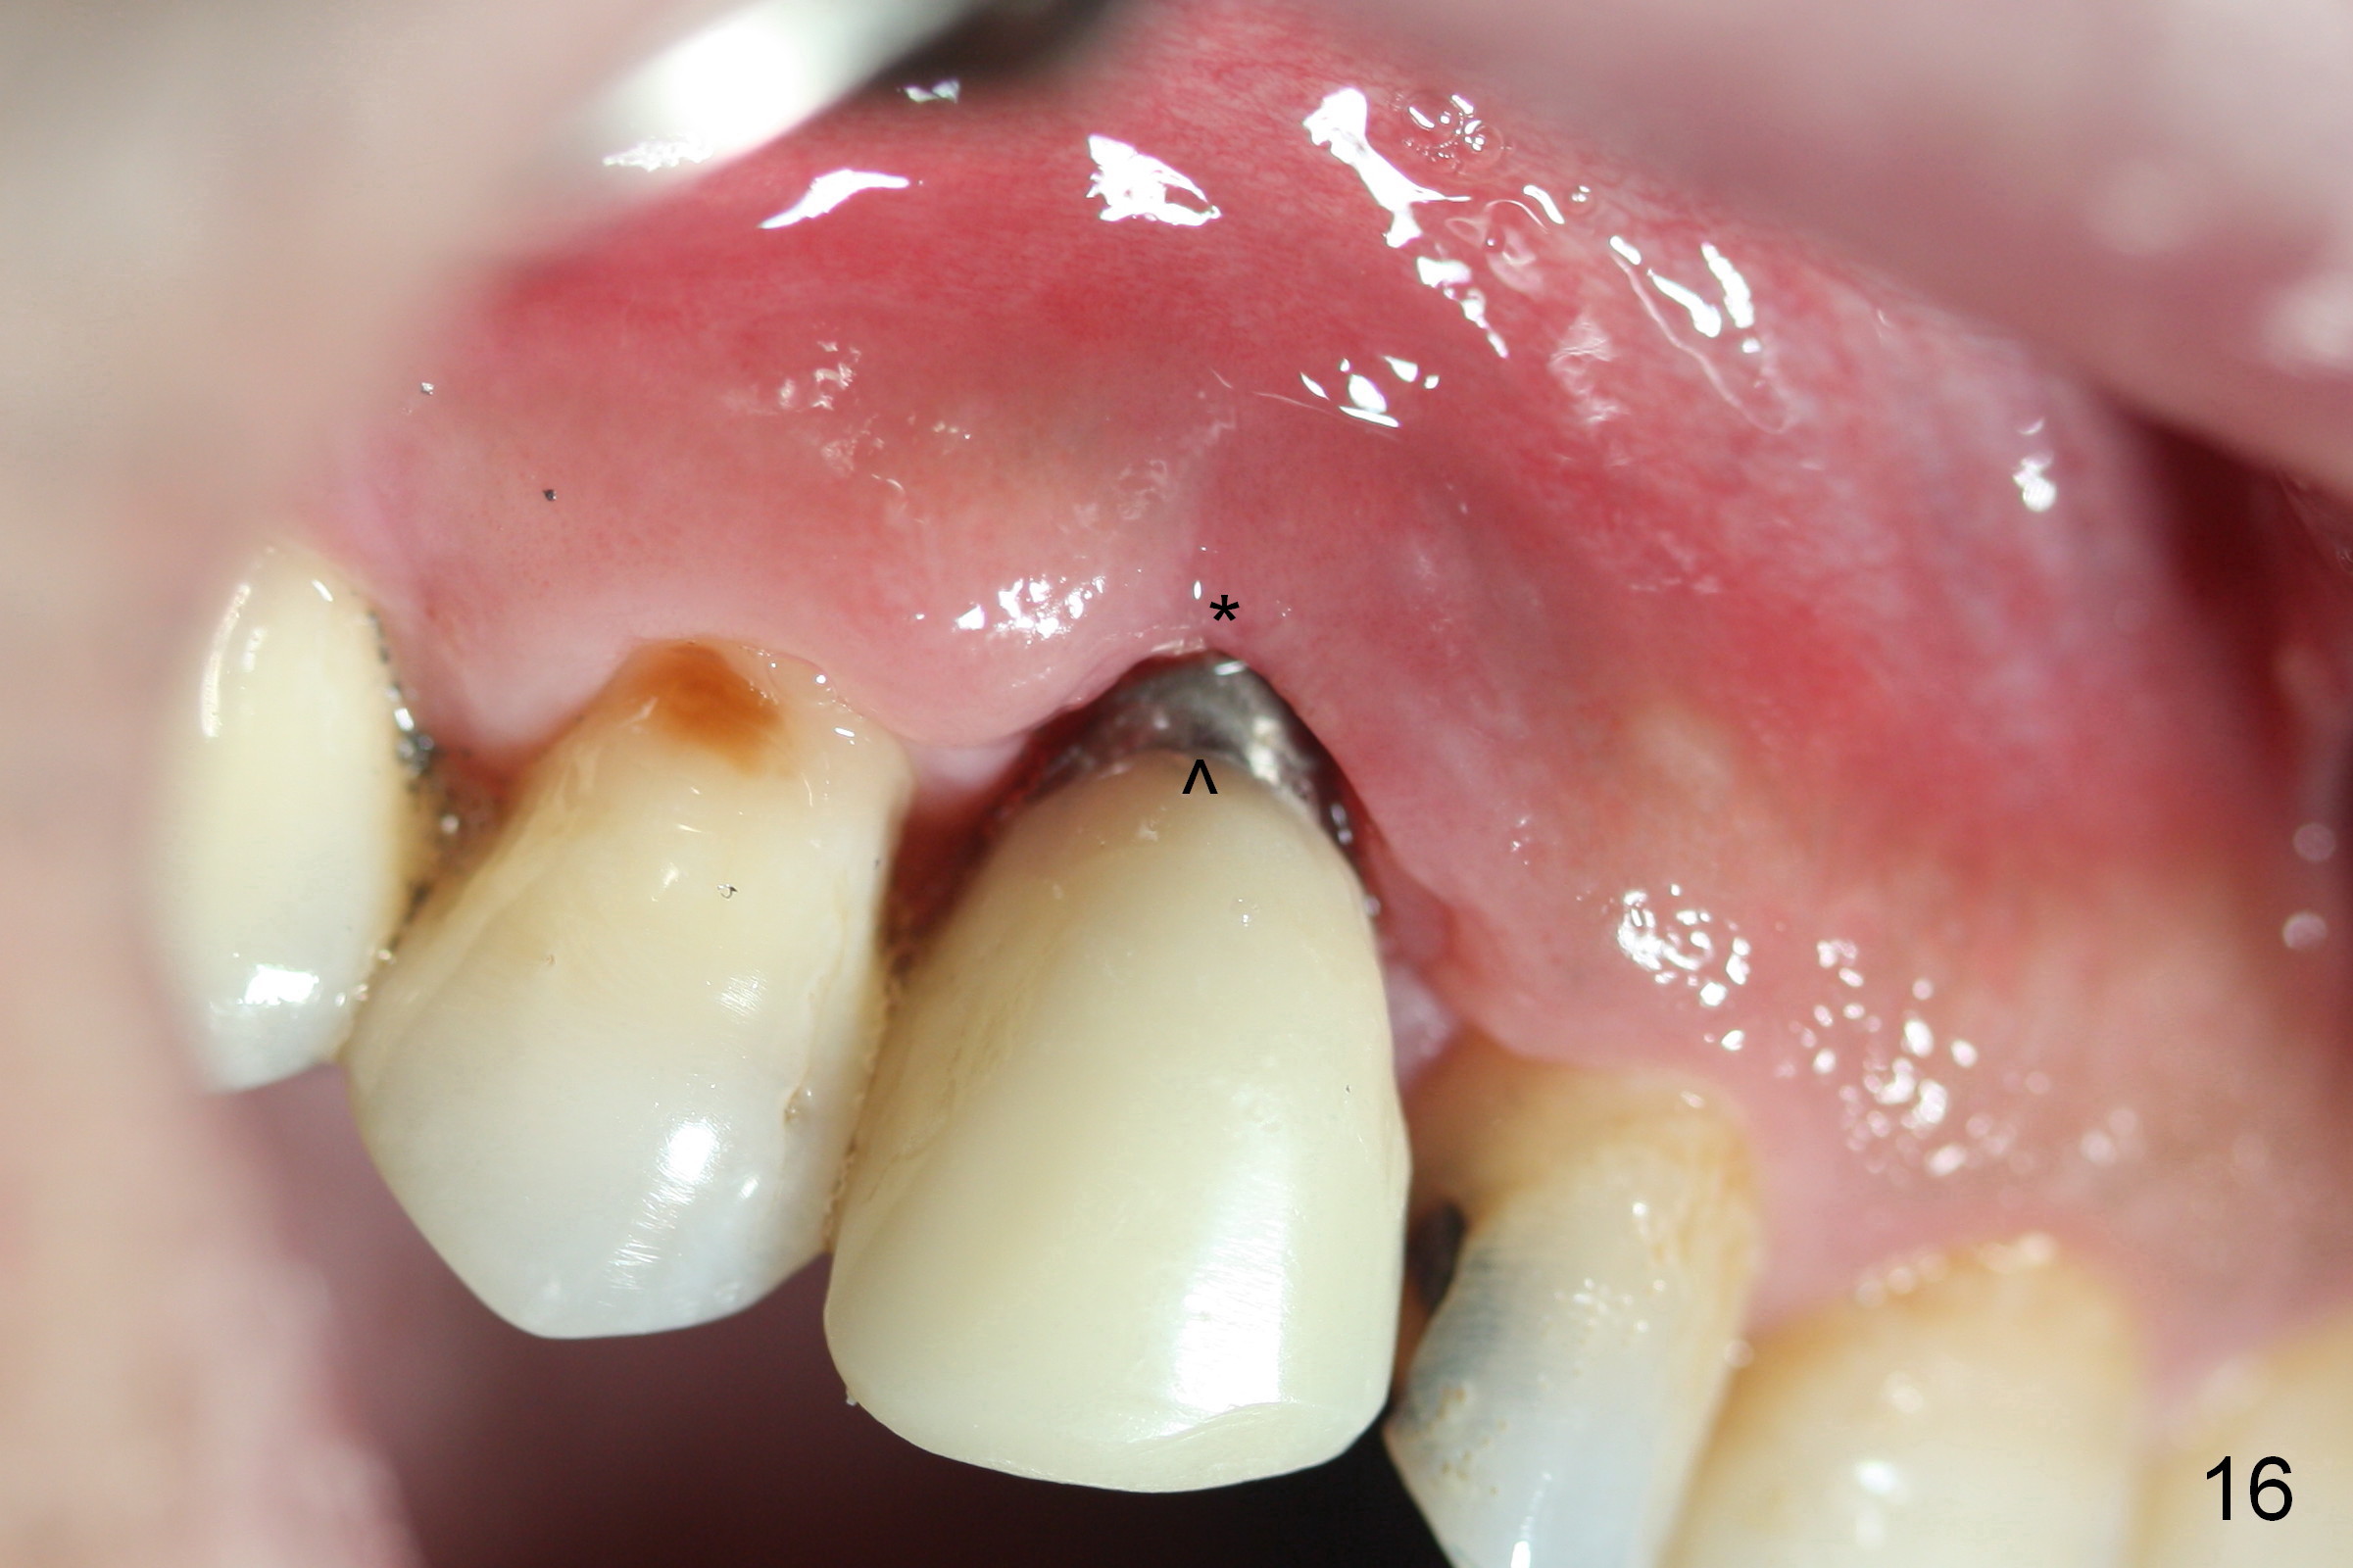

The patient returns 1.5 months postop. The provisional margin is much higher than that of the neighboring teeth (Fig.12,13: #6), unlike the opposite side (Fig.12: #11). When the provisional is removed, the implant margin is at the same level as that of the neighboring teeth (Fig.14 arrowheads). The implant margin is slightly extended apically (Fig.15 ^) prior to seating of the modified provisional. When the provisional is seated, its margin (Fig.16 ^) is at the implant margin; the gingival margin (*) is free and expected to move coronally by itself.